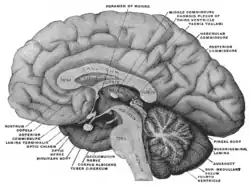

El cuerpo pineal está etiquetado en estas imágenes.

Aspecto mesal de un cerebro seccionado en el plano sagital mediano.